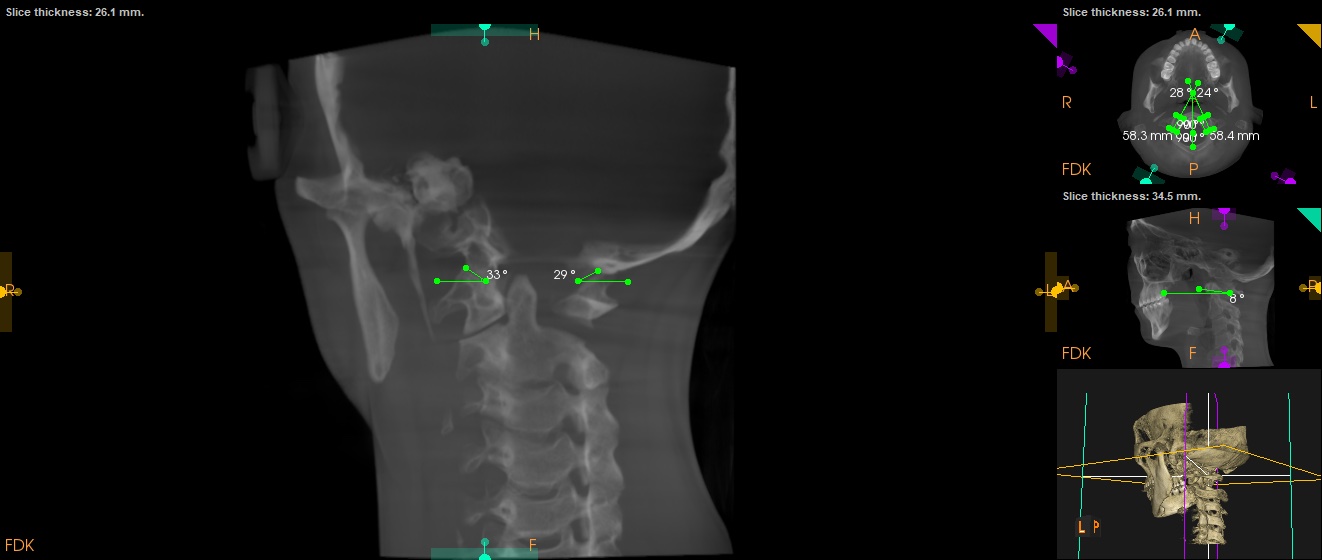

thanks @TML ! sorry to hear you are going through similar symptoms too! Heres my panoramic x-ray and CT scans that the chiropractor took. I havent got the CT imaging taken by the head and neck surgeon but hopefully they would be able to send this to me also. I saw my rheumatologist today who ordered a neck MRI/A of the vascular structures -I am unsure whether this is the correct imaging though to check for vascular compression?

@goldenretriever see attached your imaging. Both of your styloids appear elongated. One appears to be one long piece, while on the other side you have a gap where the styloid looks like a normal length but then a cm or so lower the stylohyoid ligament looks calcified.

Did the CT with the surgeon involve contrast? It doesn’t seem that the chiro CT had it. If you get one with contrast I’ll be able to help you find vascular compression!

I will say, even without contrast, I can tell your right styloid is closer to your C1 than your left styloid. Which means I suspect your right IJV and potentially vagus nerve is being compressed. Won’t know for sure without contrast though.